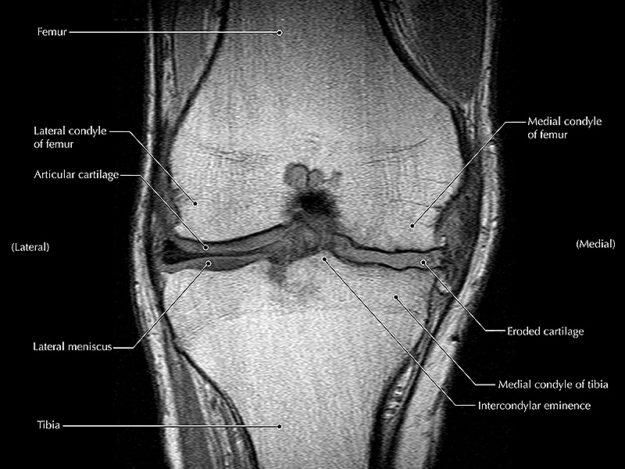

Para el 2020, la Osteoartritis u Artrosis de Rodilla Podría Afectar a 6.5 Millones de Personas en Estados Unidos

Se espera que para el 2020, tan sólo en los Estados Unidos, casi 6.5 millones de personas de entre 35 y 84 años de edad sean diagnosticadas con osteoartritis de rodilla. Más de la mitad de los nuevos casos de osteoartritis de rodilla se presentarán en personas de 45 a 65 años de edad y…